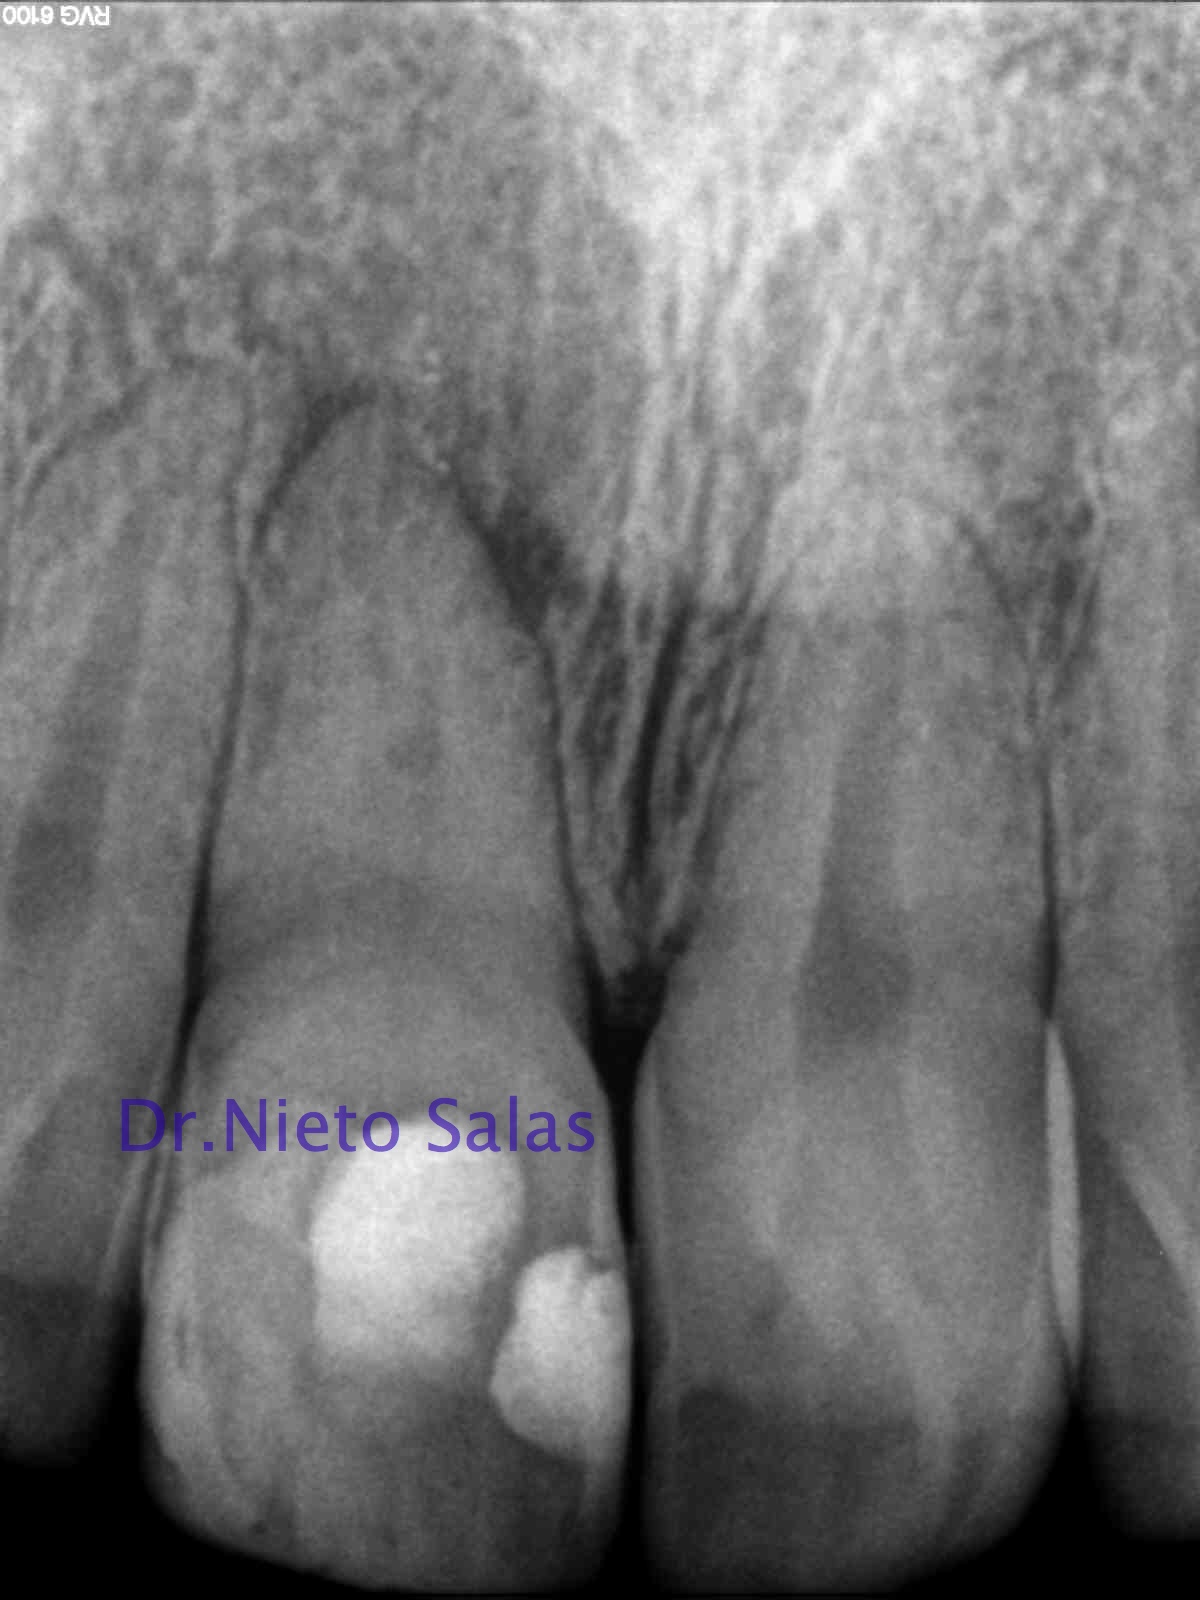

Siento mucho que no publique con una periodicidad determinada, la verdad es que intento publicar casos de interés, esta vez no es más que subir un par de casos de los que me han llegado a revisión el mes de noviembre, para mi, de mucho interés…

Se trata de un par de molares inferiores con lesiones apicales (Periodontitis apicales crónicas ). Consecuencia de caries profundas en su momento.

Se tratan del caso A y el caso B, por orden de posición, ambos casos se instrumentaron de la misma manera, elegimos Protaper hasta una F2, ambos casos se realizaron en una sesión tras abundante irrigación y finalmente se obturaron con condensación Vertical con la técnica de Ola continua de Buchanan complementando en el backfilling con guatpercha inyectada con la Pistola Obtura II.

Caso A:

Llamamos a la paciente a revisión a los 10 meses:

Caso B:

También se llamo a revisión a los 10 meses.